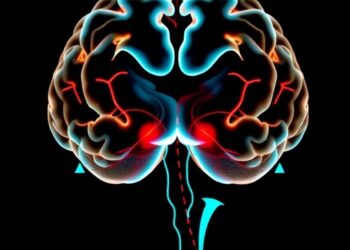

In a groundbreaking development poised to redefine our understanding of several complex neurological disorders, Dr. Rodney Scott, Division Chief of ...